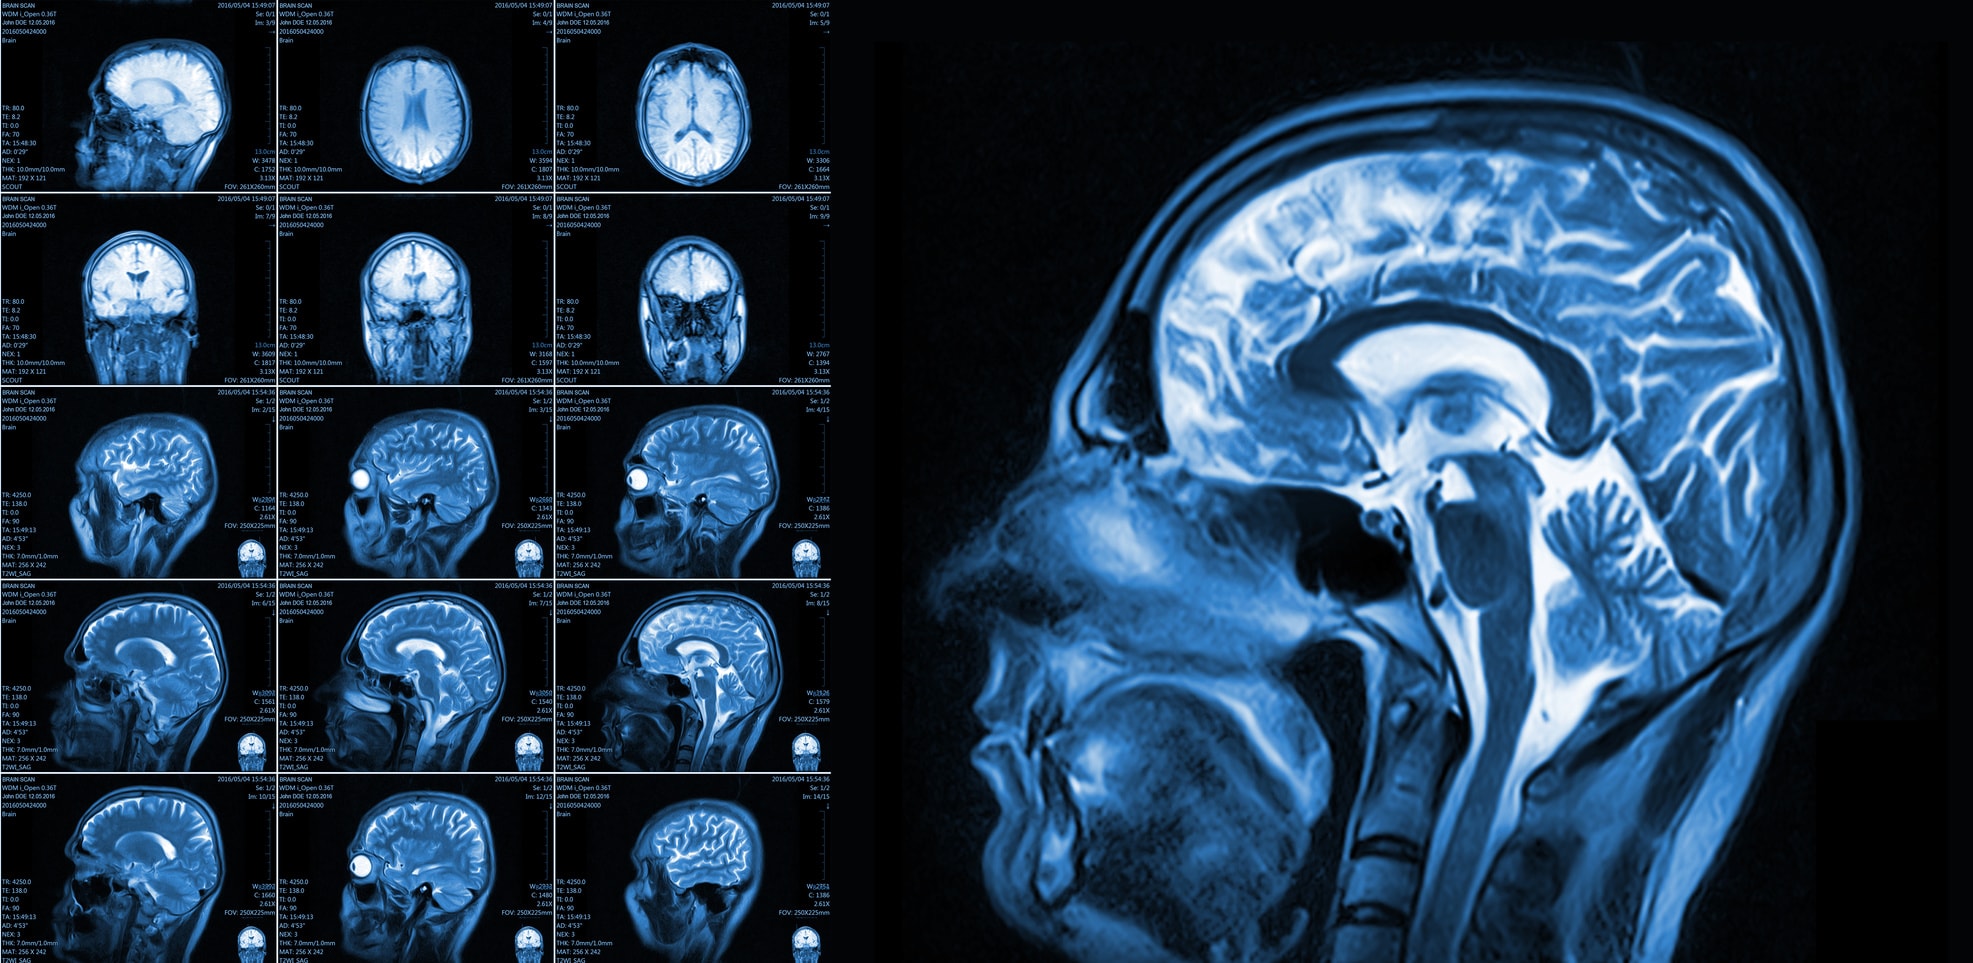

Ultrasound is an imaging technique characterized by the passing of a beam of high-frequency sound waves with low wavelength through the body to hit the organ/ tissues of interest. Based on the composition of this target tissue the waves reflect or bounce back to the detector to create tomographic images of the characteristics of the tissue. This is a non-invasive and non-radioactive technique in which the body is not subjected to the harmful effects of any ionizing radiations. This characteristic makes this technique ideal for the imaging of delicate tissues, and fetus during pregnancy. Magnetic Resonance Imaging (MRI) or Nuclear Magnetic Resonance (NMR) is also an imaging technique that evolved during the 1970s. Just like ultrasound, it does not require the use of ionizing radiation but function by creating a strong magnetic field to produce an image of spatial resolution. An MRI scanner consists of a large and powerful superconducting magnet with a 100cm bore and creating a uniform magnetic field. The magnetic field produced is about 1.5 telsa which is 30,000 times stronger than the earth’s magnetic strength. However, due to this magnetic field surrounding the object, certain atomic nuclei absorbs and emits radiofrequency energy that can be interpreted by the machine to produce a well detailed image of the object. MRI is a versatile imaging technique that is not only restricted to the medical field but also useful in chemistry to take images of both organic and inorganic structures (as in NMR spectroscopy).

Magnetic Resonance Image of the Brain

Image source

In the clinical test, the radio signals are emitted by hydrogen proton. This is because there is abundant hydrogen in body fluid composition. This proton produces two phaces of signals: first signal(T1) which is detected when the when the protons are excited by the environmental magnetc field and the second signal (T2) which is detected when the protons return back to their normal state when the magnetism is off. However the detector receives both signals (T1 & T2) and by processing their voltage difference, it produces the image of the object. Also because the protons in different tissues generate signals differently, the machine is able to create an image of these tissues with distinctions. The MRI technique is used generate an image of both anatomical structure and physiological processes. Today, X-ray images are now acquired digitally without any film. Fluoroscopy is still in use but it has advanced considerably with the use of modern image intensifier and sometimes being replaced by Computer Tomography. The old X-ray tomography has now metamorphosize into an advance Computer Axial Tomography scanning. PET is now being used with CT forming PET-CT to acquire better and more detailed metabolic information and a high spatial resolution. The PET machine designs also shows improvement in geometry; from Planar, to Polygonal to circular geometry. In big medical centres, the large volume of medical images are now being managed with PACS. Picture Archiving and Communications System (PACS) is a medical imaging management technology that makes it easier to store, access and manage images in the radiology department. ### Conclusion There has been a great evolutionary advancement since the onset of the medical imaging science. Over the last century to this moment, the medical imaging field has shown a fast trend of advancement which has really benefited the armamentarium of the medical world; there has been a great reduction of in hazards associated to the various imaging tests, production of 3D images, high resolution images, minimal time taken for the procedure and efficiency of the overall procedure. However, these improvements are not just credited to the efforts of the medical field only but also the contributions of other fields of science and technology as well as efforts of dedicated scientists. ### References - http://www.imaginis.com/faq/history-of-medical-diagnosis-and-diagnostic-imaging - https://en.wikipedia.org/wiki/Medical\_imaging - http://www.umich.edu/~ners580/ners-bioe\_481/lectures/pdfs/2008-09-procAmerPhilSoc\_Bradley-MedicalImagingHistory.pdf - https://en.wikipedia.org/wiki/Magnetic\_resonance\_imaging ---